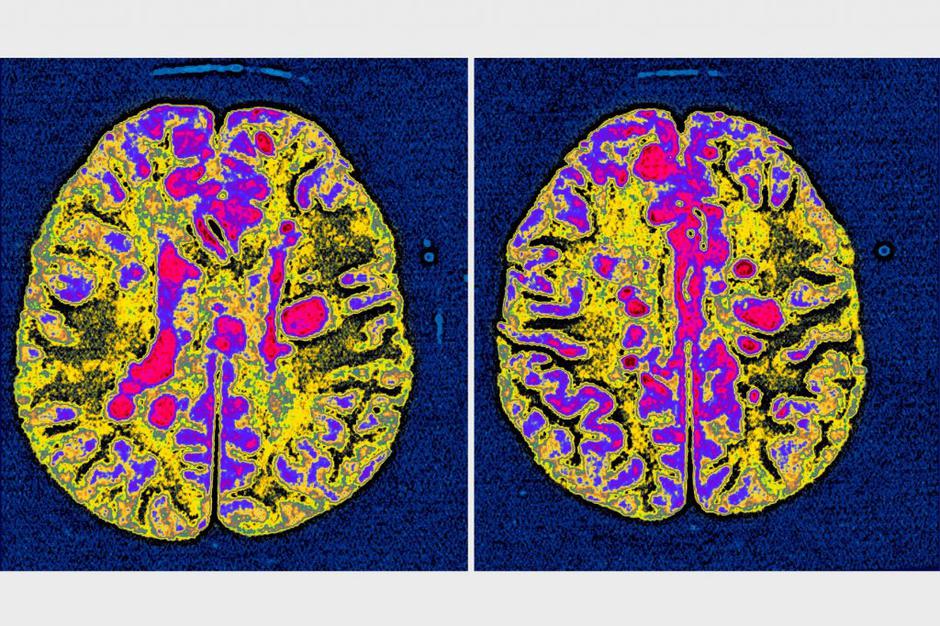

Multipla skleroza | Avtor: Profimedias Profimedias